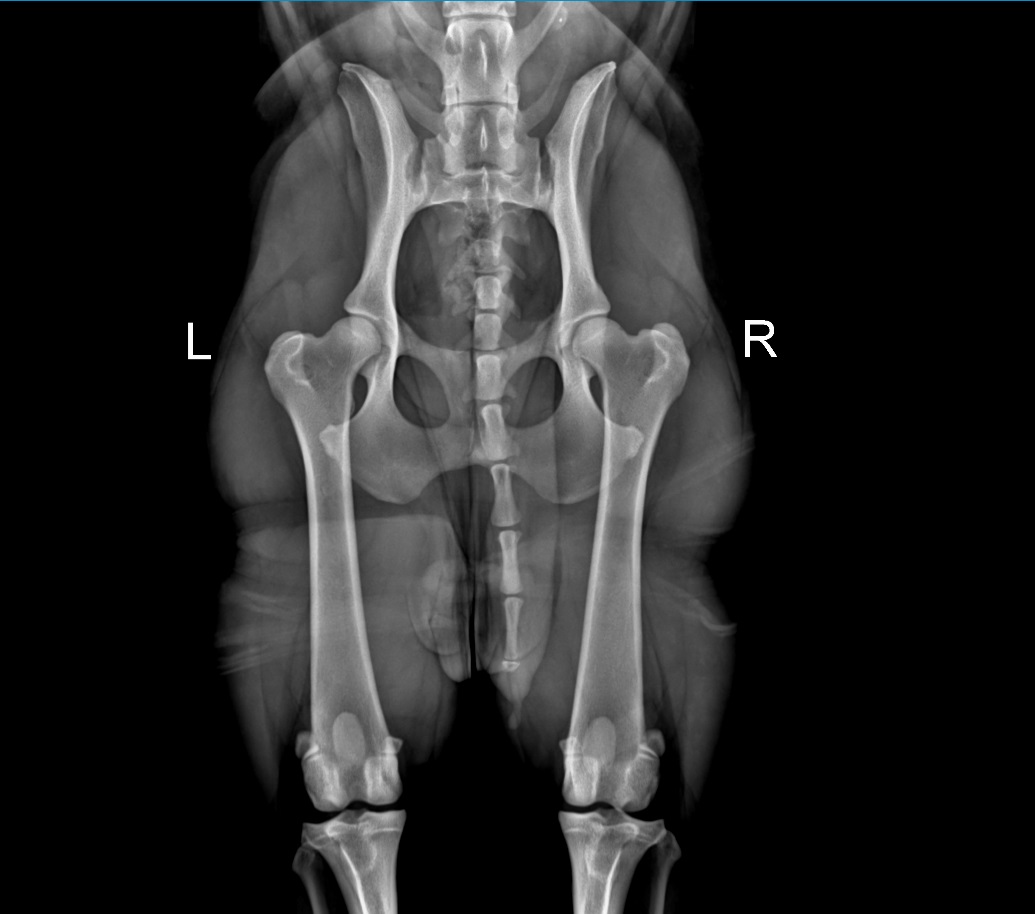

O DYSPLAZJI, CZYLI GENETYKA ILOŚCIOWA

"Dysplasia the quantitative genetics"

Artykuł skupiający się na problemie dysplazji u psów.